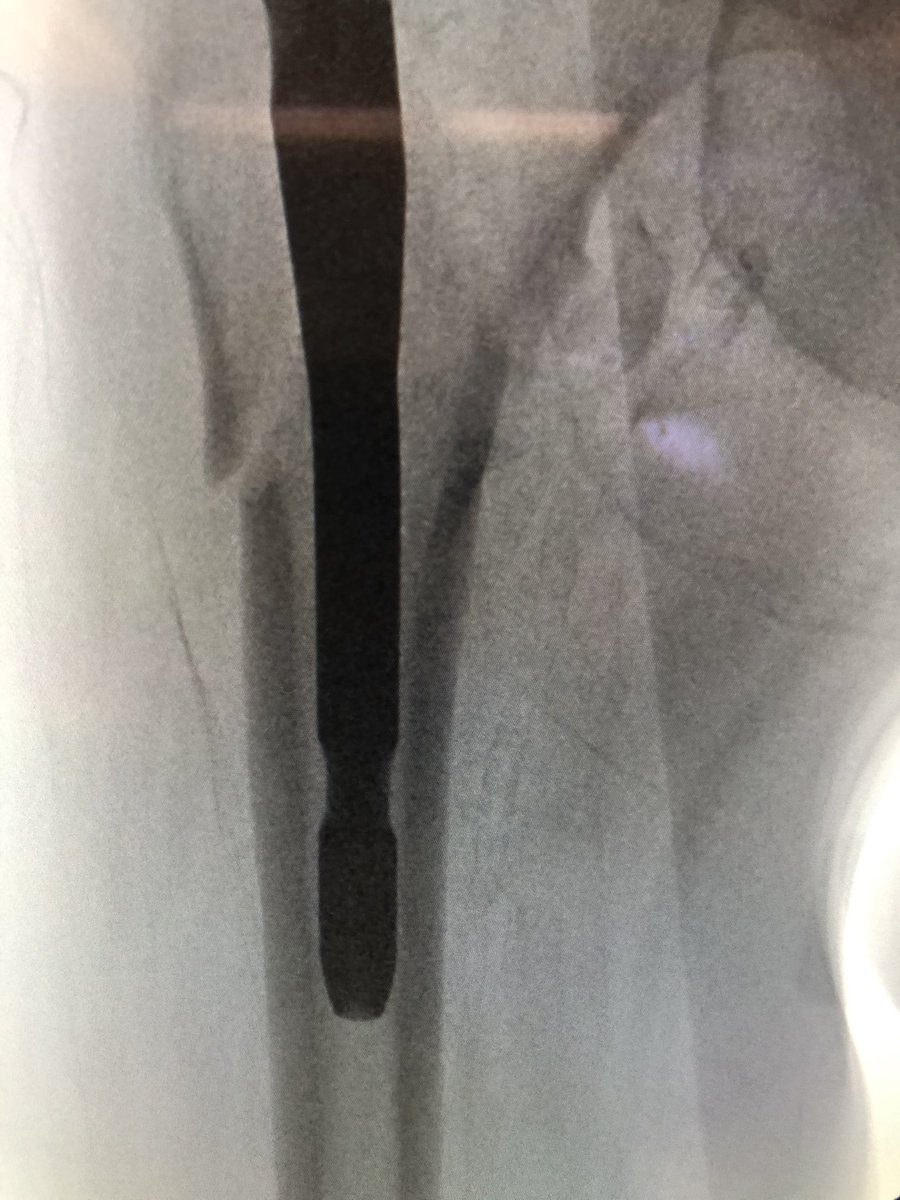

[14/18] If you line up screw handle with the line of the femur (blue) your screw end will be in the right plane. If it’s a left hip (clockwise screwing can flex the proximal fragment) I also build in an extra turn to derotate the proximal fragment if needed.